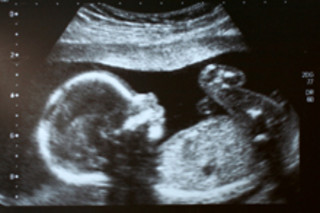

在极少数情况下,子宫对发育中的胎儿来说是一个危险的地方。研究人员发现,如果孕妇的癌细胞携带特定的基因突变,她们可以将癌细胞传给未出生的婴儿。这项新研究解决了长期存在的难题,因为理论上

任何设法穿过胎盘进入婴儿血液的癌细胞都应该被孩子的免疫系统定向摧毁。但有记录显示,有17例母亲和婴儿似乎患有相同的癌症——通常是白血病或黑色素瘤 [英国广播公司新闻]。

在即将发表于美国国家科学院院刊的研究中,研究人员使用了一种基因“指纹”技术来匹配在母亲和婴儿体内发现的癌细胞。

该病例涉及一位28岁的日本母亲和她的女儿,结果显示,两位患者的白血病细胞都携带相同的突变癌基因BCR-ABL1,尽管婴儿没有遗传这种基因 [泰晤士报]。

这意味着,在11个月大时被诊断出癌症的儿童不可能独立患上白血病。为了确定癌细胞如何避免被婴儿的免疫系统摧毁,研究人员观察了孩子体内的癌细胞,发现了一个缺失突变——一些DNA缺失的地方。这种突变发生在区分个体细胞的基因区域,这意味着婴儿的免疫系统没有将癌细胞识别为异物,也没有摧毁它们。这项研究中检查的特定病例只有一个不太圆满的结局。

这位母亲在分娩后被诊断出患有白血病,并于去年几周后去世。这位女婴患上了颌部肿瘤,该肿瘤被证实带有与母亲癌症相同的基因标记,经过 intensive 治疗后恢复良好 [泰晤士报]。

但首席研究员梅尔·格里夫斯不想让孕妇再多一件需要担心的事情;他说

“这种癌症从母亲到后代的转移极其罕见,任何患有癌症的孕妇将其传给孩子的几率都很小” [英国广播公司新闻]。